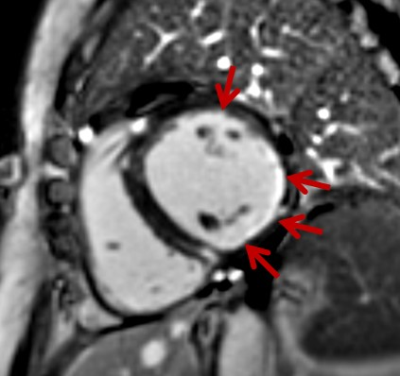

A 47-year-old woman with polymyositis. Late gadolinium enhancement image showed intramural contrast in ventricular septum and transmural contrast in lateral wall of the left ventricle.